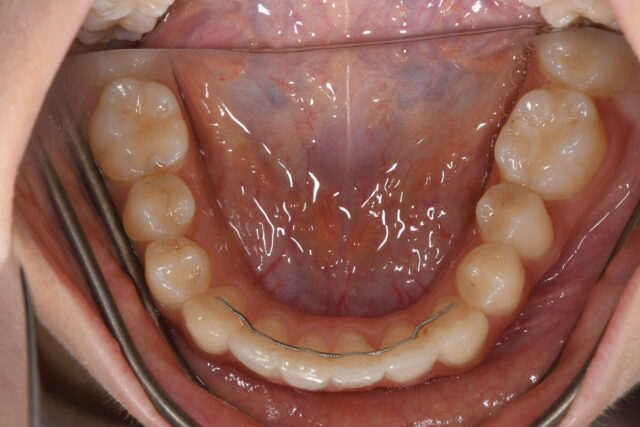

矯正前(下顎)

矯正後 保定期間中(下顎)